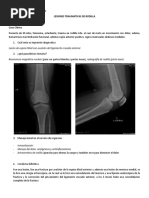

tensión. Su causa es ruptura de L.C.A, fractura Fractura de rodilla

intraarticular. Clínica: en la exploración física destaca el

• Se observan gotas finas de grasa en la dolor en la cara anterior de la rodilla con

superficie del materia hemático de la tumefacción, siendo habitual la ocupación

punción, desinserción periférica de un articular por hemartros. La palpación de la

menisco (zona roja) → ruptura de la rótula bajo la piel puede mostrar la localización

membrana sinovial o pctes hemofílicos. del punto de máximo dolor y un defecto o

Derrame seroso separación de los fragmentos en caso de ser una